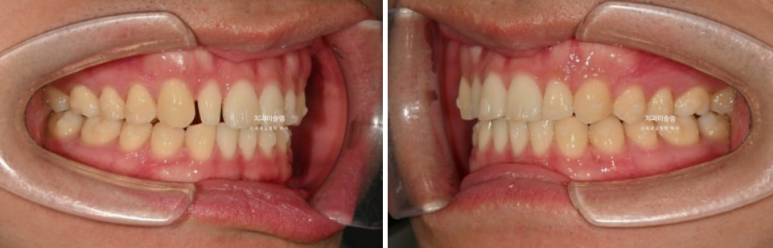

24.03~25.11

어금니 교합은 기존 2급에서 1급 교합관계를 달성

물샐틈 없는 교합은 교정치료의 기본입니다.